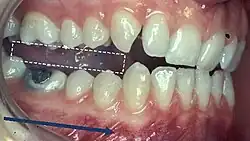

5) Contacts in ICP

Begin by assessing the incisor and molar relationship as described above. Similarly examine the overbite and overjet. An overbite of 3-5mm[2] and an overjet of 2-3mms are considered to be within the range of normal.[13]

To look at the ICP, articulating paper should be placed on the occlusal surface and the patient asked to bite together, which will mark their occlusal contacts. It is best to check these whilst the teeth are dry.

- During ICP, most opposing teeth should be contacting[2]

- Close examination of these contacts marked by the articulating paper help to identify the nature of the tooth contacts

- Good stable contacts often appear as small and not very prominent markings when articulating paper is used and there are multiple contacts on each tooth

- Broad and rubbing contacts identified in ICP may be associated with disturbances in function and may indicate occlusal instability[25]

- These contacts can be verified using Shimstock (a 12.5μm thick mylar strip) and the stability of the contacts can be checked

- The operator should pull the Shimstock through the teeth, whilst the patient is biting together

- This should be carried out for each set of teeth and will highlight if there is adequate contact to hold the Shimstock

- This material is appropriate as it is thinner and will eliminate any false contacts that may occur with even thin articulating papers that are roughly 20μm thick

- One is also able to pull shim stock through when patients are biting together unlike other articulating paper, which will tear